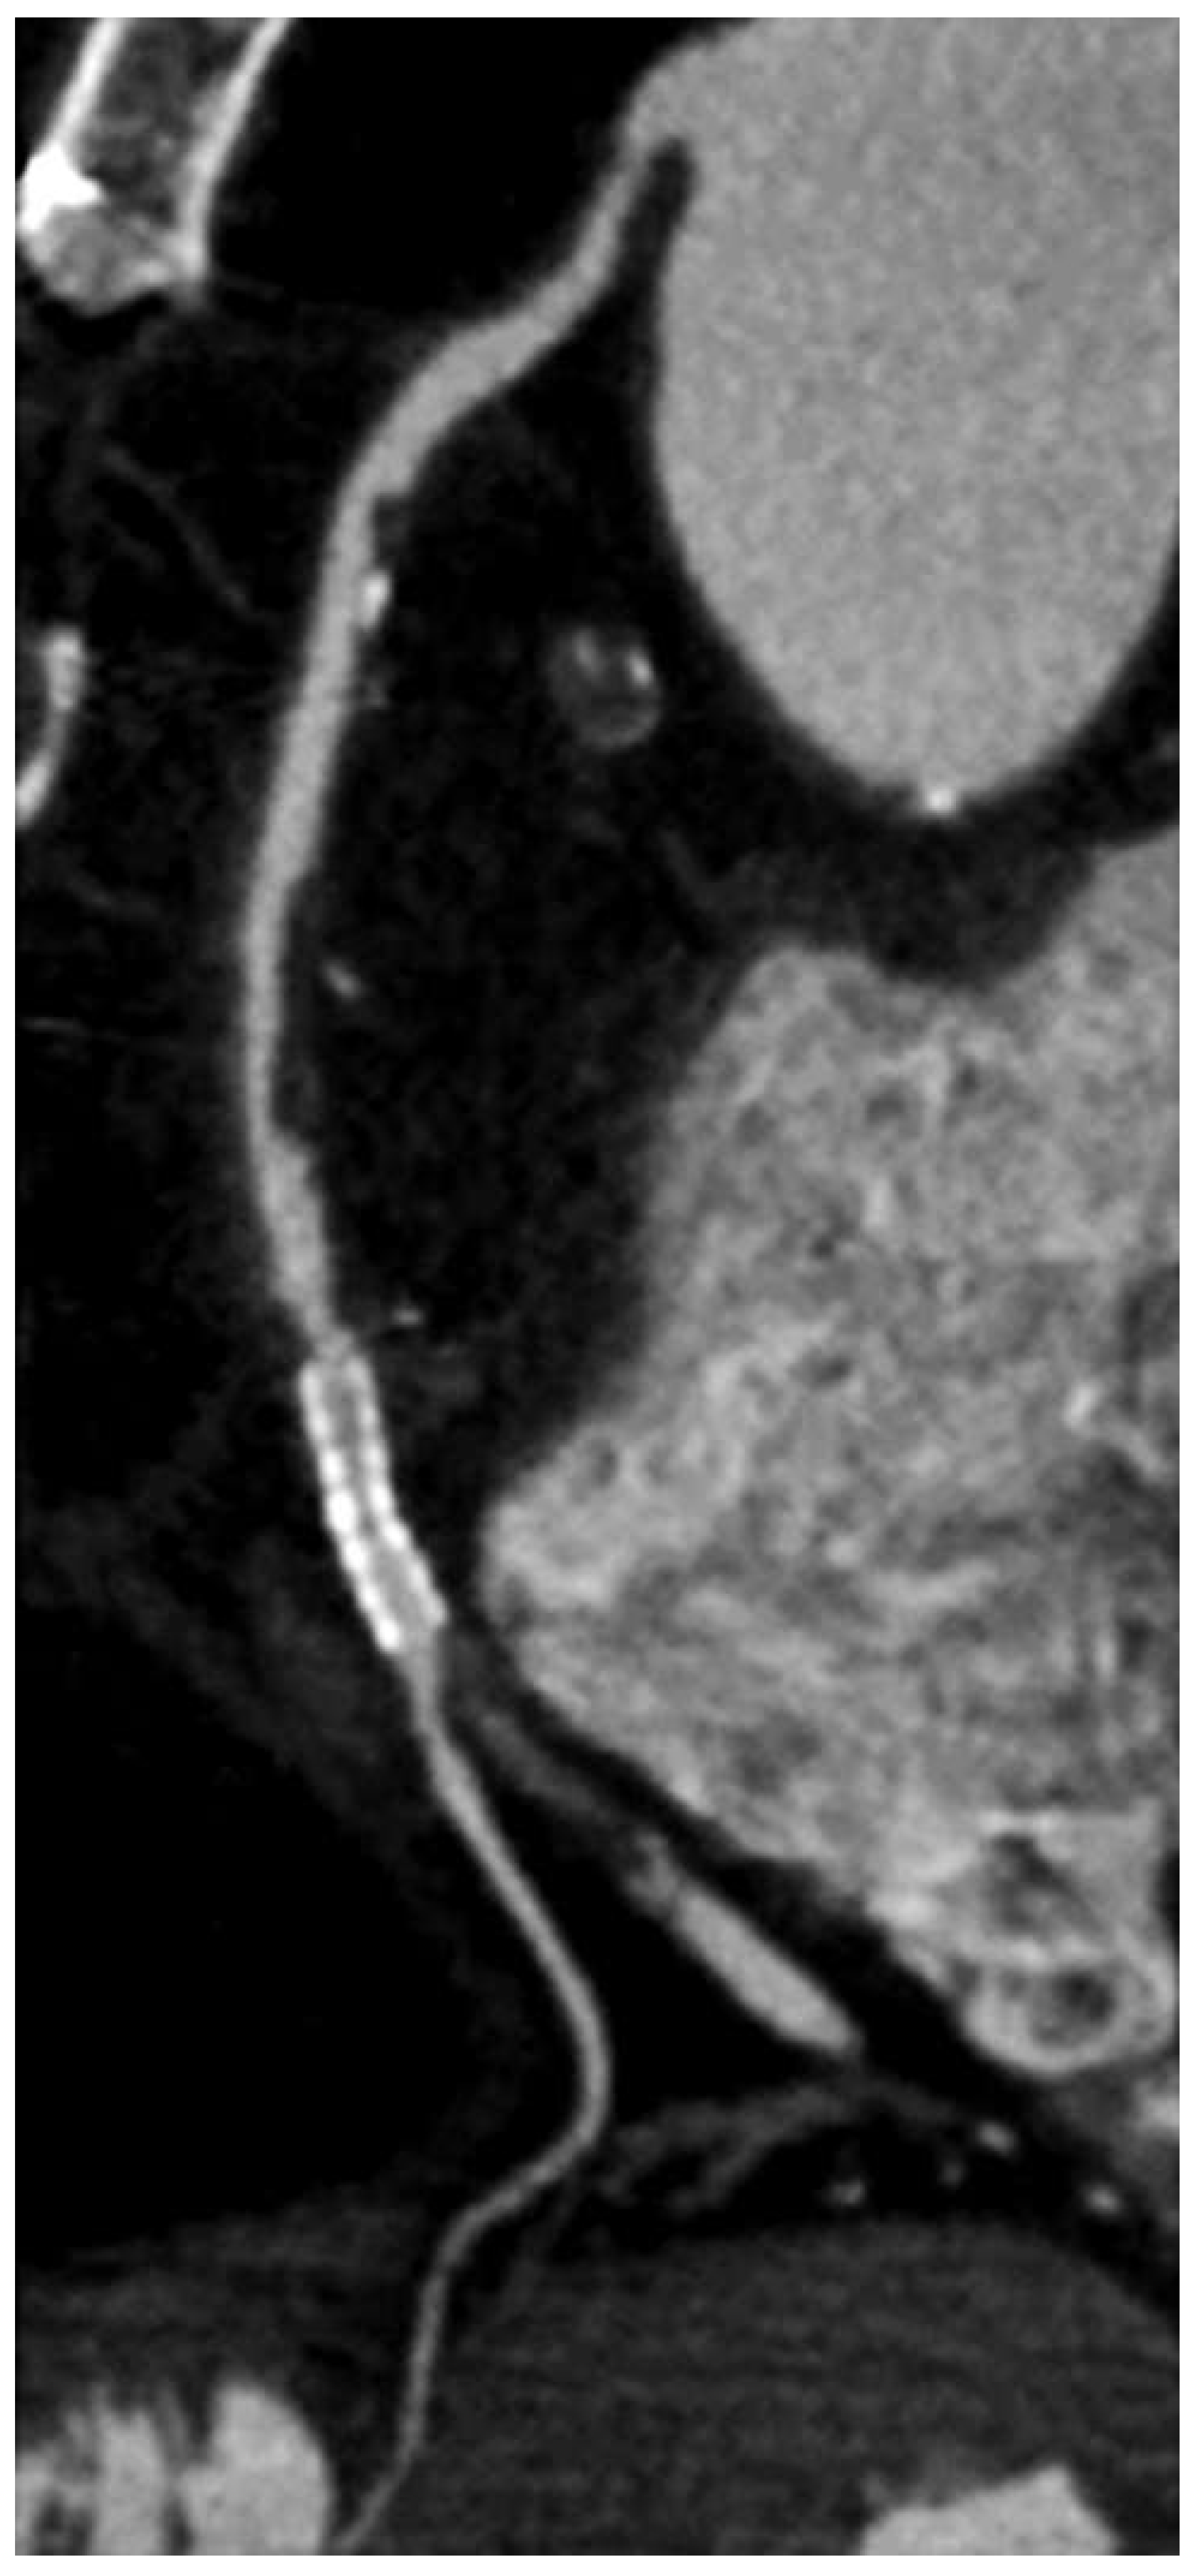

Contrast-enhanced coronary imaging with CT

Diagnostic accuracy of CTCA for coronary artery disease

The importance of CTCA and other imaging modalities in determining the risk of cardiac death / myocardial infarction (MACE) and allcause mortality